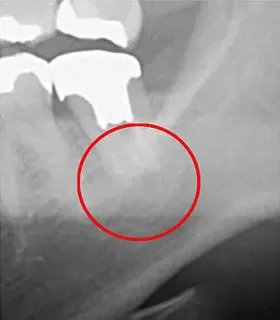

下の画像をご覧ください。

こちらは CT画像(左)とデンタルレントゲン(右)の比較です。丸印を付けた部分が問題の箇所ですが、右側のデンタルレントゲンでは黒い影が映っておらず、異常を見落としてしまう可能性があります。

問題の部位を発見できなければ、当然ながら適切な治療を行うことはできません。

治療できない箇所を残したままにすると、それが再発の原因となってしまいます。

根管治療において重要なのは、「見えるかどうか=可視化できるかどうか」です。

この可視化の有無こそが、治療の成功を大きく左右する要因となります。